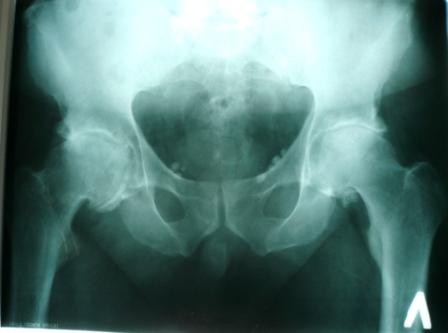

Больной Т. 56 лет, Диагноз: двухсторонний коксартроз 3-4 ст справа, 1-2 ст слева 2.10.08 выполнена операция тотальное бесцементное эндопротезирование. Использовался наружный доступ, положение на боку. Операция протекала без особенностей.

Выполнен послеоперационный ренгеноконтроль в прямой проекции